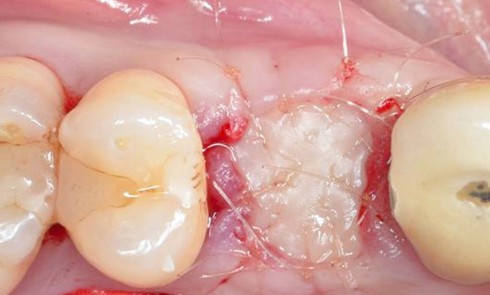

- Péri-implantite sur l’implant 47, diagnostiquée en août 2022

- Poches de 6 à 7 mm

Actes préopératoires

La couronne a été déposée et une vis de couverture mise en place. La patiente a reçu un nettoyage supra-gingival général avec une attention particulière pour l’implant 47, et une irrigation locale avec du gel de chlorhexidine et du peroxyde d’hydrogène pour réduire l’inflammation des tissus. De l’amoxicilline (3 x 500 mg) a été prescrite, à commencer la veille de l’intervention chirurgicale.